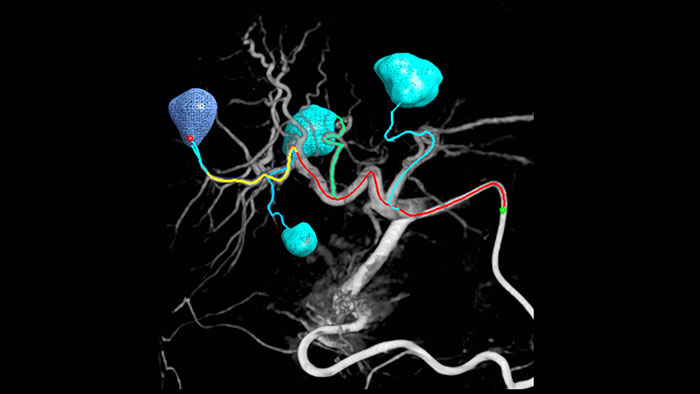

Unsere dedizierte Lösung verbessert die Erkennung von Versorgungsgefäßen signifikant. Mit EmboGuide können Sie die Effizienz Ihrer TACE-Verfahren maximieren, da die Funktion die Empfindlichkeit verbessert, falsch positive Ergebnisse reduziert und eine höhere Konsistenz zwischen den befundenden Medizinern ermöglicht.1 Darüber hinaus bietet EmboGuide eine Arbeitsablauf-basierte Live-3D-Führung mit automatischer Erkennung der Versorgungsgefäße1.

Chemo-/Radioembolisationsverfahren wie TACE und SIRT erfordern eine höhere Standardisierung und Effizienz. Die Tumore müssen jedes Mal zuverlässig und konsistent lokalisiert, alle Versorgungsgefäße erkannt und die geeigneten interventionellen Maßnahmen geplant und durchgeführt werden. Unsere dedizierte Lösung kann die Erkennung von Versorgungsgefäßen im Vergleich zur alleinigen Verwendung von Cone-Beam-CT signifikant verbessern. Für möglichst effiziente TACE-Verfahren kann EmboGuide die Empfindlichkeit verbessern, falsch positive Ergebnisse reduzieren und eine höhere Konsistenz zwischen den befundenden Medizinern gewährleisten.1

Für die Wahl der richtigen Behandlung ist es unerlässlich, hepatische Rundherde zu erkennen und zu differenzieren und auch kleinste Versorgungsgefäße zu identifizieren. Mit der Möglichkeit, den relevanten Bereich und alle Versorgungsgefäße zu erreichen und dabei läsionsselektiv zu bleiben, erhöht sich die Wahrscheinlichkeit eines Behandlungserfolgs. Wenn schließlich Behandlungsendpunkt und Behandlungserfolg bestätigt werden können, während sich der Patient noch auf dem Untersuchungstisch befindet, erhöht sich die Sicherheit des Behandlungsausgangs.